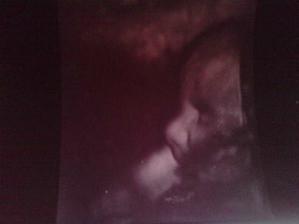

Naše prvé